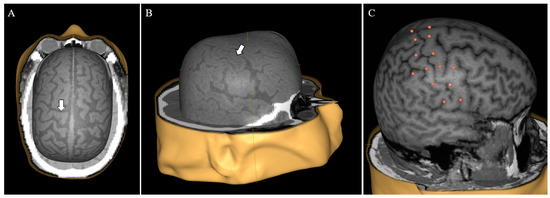

To make CT scans viable for use in the nTMS system, we performed a series of preprocessing steps (removal of non-patient structures such as e.g., headrest, proper windowing, intensity rescaling) using the Aliza Medical Imaging and DICOM Viewer (Aliza 1.98.12, Copyright 2014–2020 Aliza Medical Imaging, Bonn, Germany), the details of which are available as Supplementary Material (Document S1). The exported DICOM files were loaded into the nTMS system (Nexstim eXimia NBS system, version 4.0; Nexstim Plc., Helsinki, Finland) and used to create head models (Figure 1A,B).

In order to validate the use of CT imaging compared to the standard MRI imaging, we compared the e-field calculated by the system in both modalities in four sets of imaging data. For each head model, 26 stimulation targets were put on the cortical surface, distributed around the central sulcus (Figure 1C). The virtual model was co-registered to a dummy head in 3 cases and to the actual patient in 1 case. Each target was subsequently stimulated with an intensity of 30% of maximum stimulator output and the calculated local maximum e-field was recorded. This specific stimulation intensity was selected since 30% of maximum stimulator output is a common benchmark for motor thresholds in neurosurgical motor mappings.

A prerequisite for nTMS motor mapping is preexisting cranial imaging used for neuronavigation. In the conventional workflow, MRI offers unparalleled anatomical imaging of brain tissue with a high soft tissue contrast, and it is, therefore, the gold standard for navigational imaging [8]. MRI, however, is oftentimes not a viable option for ICU patients due to practical considerations or contraindications for scanning. Specifically, critically ill patients are often unable to tolerate lengthy MRI studies. Furthermore, intracranial monitoring devices such as cranial bolts and indwelling electrodes can be incompatible with the scanning environment [29]. Although it offers less detailed imaging of intracranial anatomy than MRI, CT is by far the more prevalent modality for patients in the ICU due to its rapid acquisition time and compatibility with clinical equipment [29,30]. Therefore, to enable widespread use of nTMS motor mapping in the ICU, we realized that CT must be adapted and validated as the basis for neuronavigation. Using CT for this purpose has previously only been described in a singular recent case which did not address possible navigation discrepancies between CT and MRI [31]. By preprocessing CT scans with a slice thickness of 2 mm, we were able to generate usable head models suited for patient co-registration (Figure 1). Comparing the calculated maximum e-field at corresponding points in CT head models to that in MRI head models, we found no significant difference in calculated e-field values. While the maximum difference between two points was 18 V/m, we believe that this discrepancy was likely an artifact due to the inherent difficulty of co-registering a given head model to a physical dummy with different measurements. Our results indicate that both CT and MRI can yield comparable neuronavigation in the employed nTMS system. Following our process enables targeted, replicable stimulation of given brain loci in patients lacking MRI data. This application of CT-based neuronavigation not only makes motor mapping in the ICU an option, but also extends nTMS usage to any patient unable to undergo MRI (because of retained metal fragments, implanted devices, etc.).

Figure 1. Head model based on computed tomography (CT). By using appropriate preprocessing, CT can serve as a viable basis for head model reconstruction in the nTMS system (A,B). Important anatomical structures such as the precentral gyrus are easy to identify (A,B, white arrows). For image testing, 12 targets were placed around the central sulcus on each hemisphere with two additional targets at the midline vertex (26 targets total per brain, C).